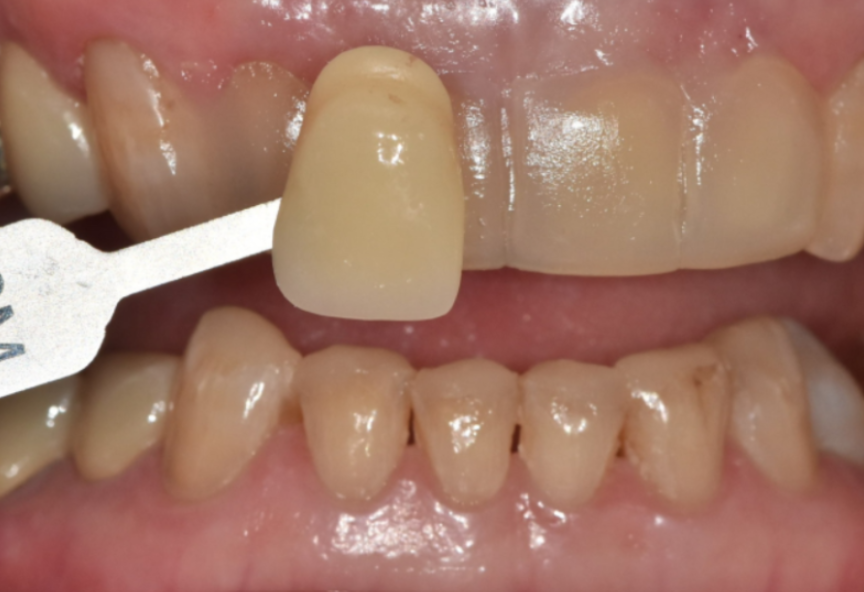

저희 치과는 원내 기공실을 운영하고 있어

라미네이트 보철을 외부 기공소로 보내지 않고

병원 안에서 직접 제작하고 있습니다.

그래서 진료실에서 본 실제 치아 상태와

기공 과정이 자연스럽게 이어집니다.

치료하는 의사가

기공 과정 전반에 직접 참여하면서

라미네이트의 두께, 형태, 길이,

그리고 색감과 투명도까지

환자분 얼굴과 기존 치아에 어울리도록

세밀하게 맞춰 갈 수 있습니다.

또 시적(끼워 보는 과정) 후

말할 때나 웃을 때 느낌을 바로 확인하고,

필요하면 그 자리에서 기공실과 상의해

조금 더 다듬어 드릴 수 있습니다.

이번 70대 환자분도

이 과정을 통해

과개교합에서 오는 힘을 분산시키면서도

왜소치와 벌어진 앞니를 자연스럽게 정리하는

맞춤 라미네이트를 완성할 수 있었습니다.